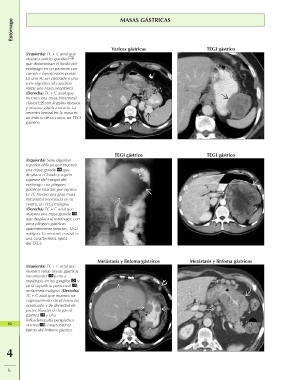

(Izquierda) TC + C axial que Varices gástricas TEGI gástrico

muestra varices grandes

que distorsionan el fondo del

estómago en un paciente con

cirrosis e hipertensión portal.

En una TC sin contraste o una

serie digestiva alta podrían

imitar una masa neoplásica

(Derecha) TC + C axial que

muestra una masa intramural

clásica con ángulos obtusos

y mucosa gástrica intacta. La

necrosis central en la masa es

un indicio de su causa, un TEGI

gástrico.

(Izquierda) Serie digestiva TEGI gástrico TEGI gástrico

superior oblicua que muestra Metástasis y linfoma gástricos Metástasis y linfoma gástricos

una masa grande que

desplaza el fondo y región

superior del cuerpo del

estómago con pliegues

gástricos intactos por encima

La TC mostró una gran masa

intramural necrosada en su

centro, un TEGI maligno.

muestra una masa grande

que desplaza el estómago, con

unos pliegues gástricos

aparentemente intactos; TEGI

maligno. La necrosis central es

una característica típica

del TEGI.

(Izquierda) TC + C axial que

muestra varias masas gástricas

intramurales junto a

metástasis en los ganglios y

en la superficie peritoneal ;

melanoma maligno. (Derecha)

TC + C axial que muestra un

engrosamiento circunferencial,

acentuado y de densidad de

partes blandas de la pared

gástrica y una

linfoadenopatía perigástrica

82 extensa , características

típicas del linfoma gástrico.